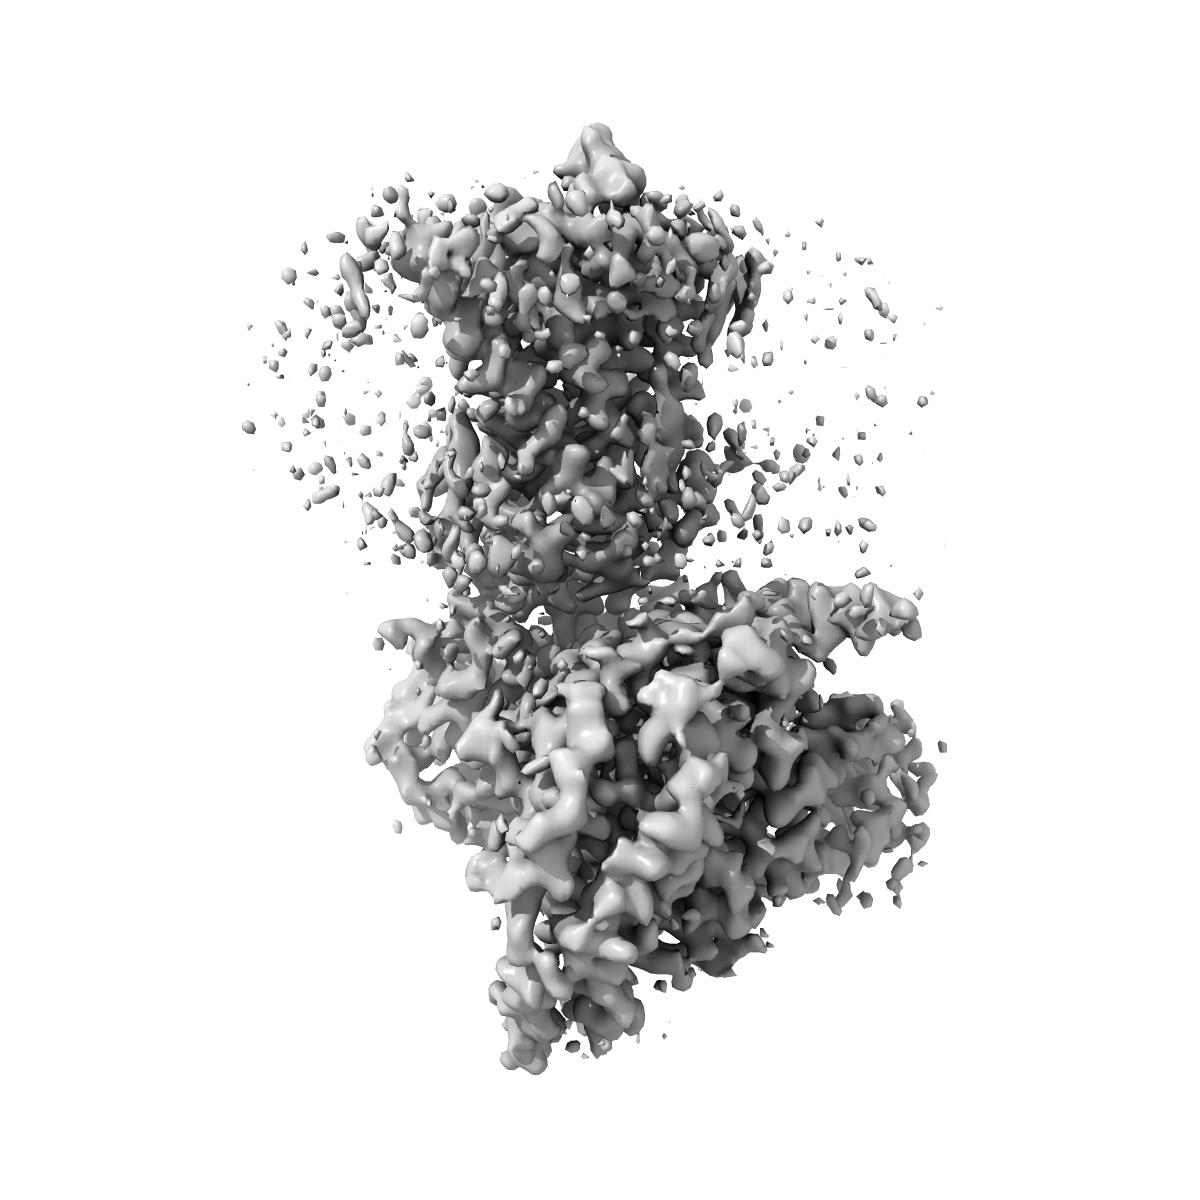

CryoEM structure of beta-2-adrenergic receptor in complex with GTP-bound Gs heterotrimer (Class B)

Sample: Complex of beta-2 adrenergic receptor and Gs heterotrimer with GTP

Time-resolved cryo-EM of G-protein activation by a GPCR.